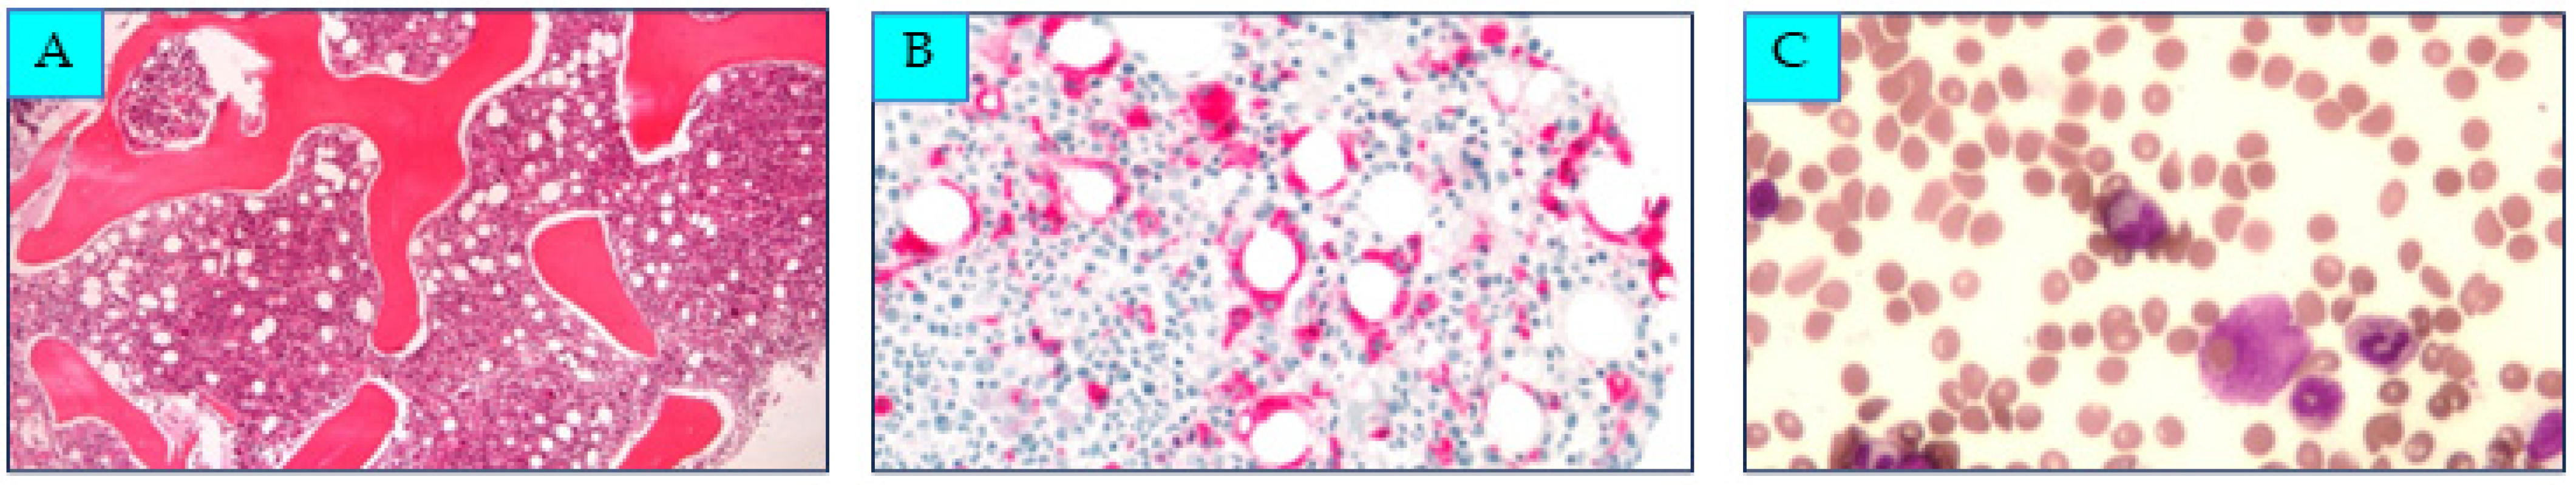

2. Case Presentation